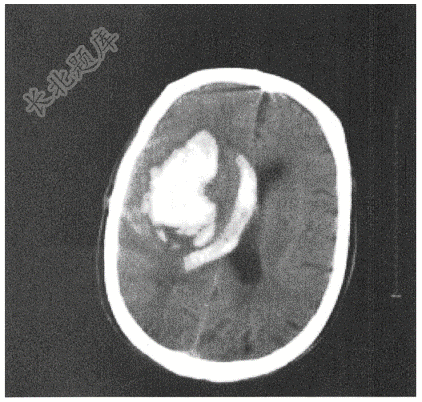

- 简答题患者男性,61岁,既往高血压病史,突发昏迷2小时就诊。急查头颅CT如下: